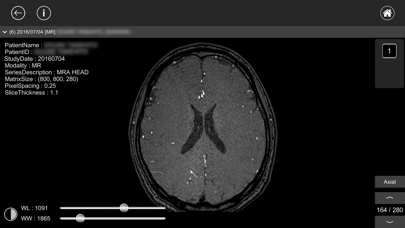

【閲覧モード】

- ウインドウレベルの調整、画像の拡大・平行移動がタッチ操作で簡単に行えます。

- CTやMR画像などは横断面(Axial)から再構成した冠状面(Coronal)、矢状面(Sagittal)画像を閲覧することができます。(3次元再構成)

【閲覧モード】

- ウインドウレベルの調整、画像の拡大・平行移動がタッチ操作で簡単に行えます。

- CTやMR画像などは横断面(Axial)から再構成した冠状面(Coronal)、矢状面(Sagittal)画像を閲覧することができます。(3次元再構成)